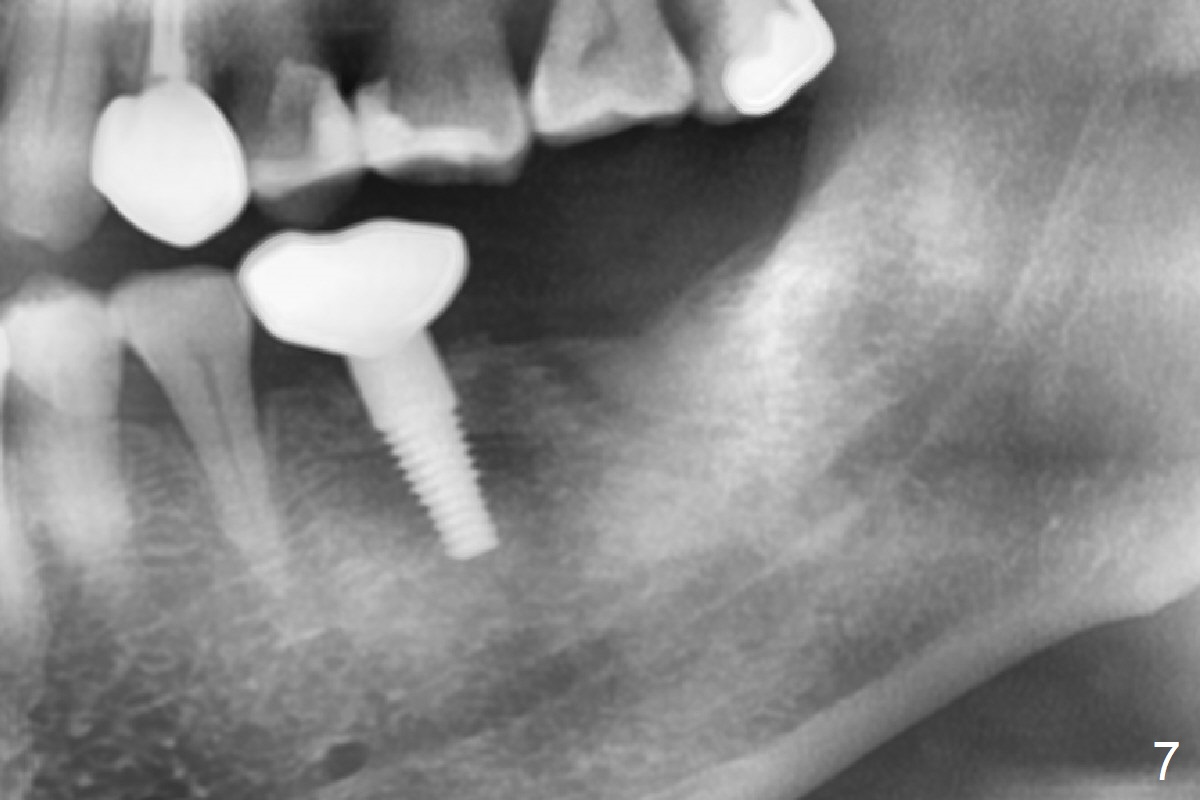

Due to severe furca (Fig.1 *) and distal root (Fig.2 D) infection at #31, there is pain when osteotomy is initiated in the apical native bone for 2 mm after extraction (Fig.3). The distal root is found to have vertical fracture. Socket preservation is performed with Vera Graft, collagen plug and 6-month membrane (Fig.4). In fact it would be possible to initiate osteotomy (Fig.5 white line) in the mesial slope (red dashed line) for implant placement (less infection (far from the lesion), less pain). There is postop pain and swelling, but the symptoms are less 7 days postop (Fig.6). The patient returns 6 months post socket preservation (Fig.7). The bone density at the healed socket is high (>1000 units); a 5x10 mm implant will be placed with guide (Fig.8). After implant placement at #18, make a buccal incision to explore the buccal gingival defect at #19 (Fig.9, 1), most likely due to extra bone graft.